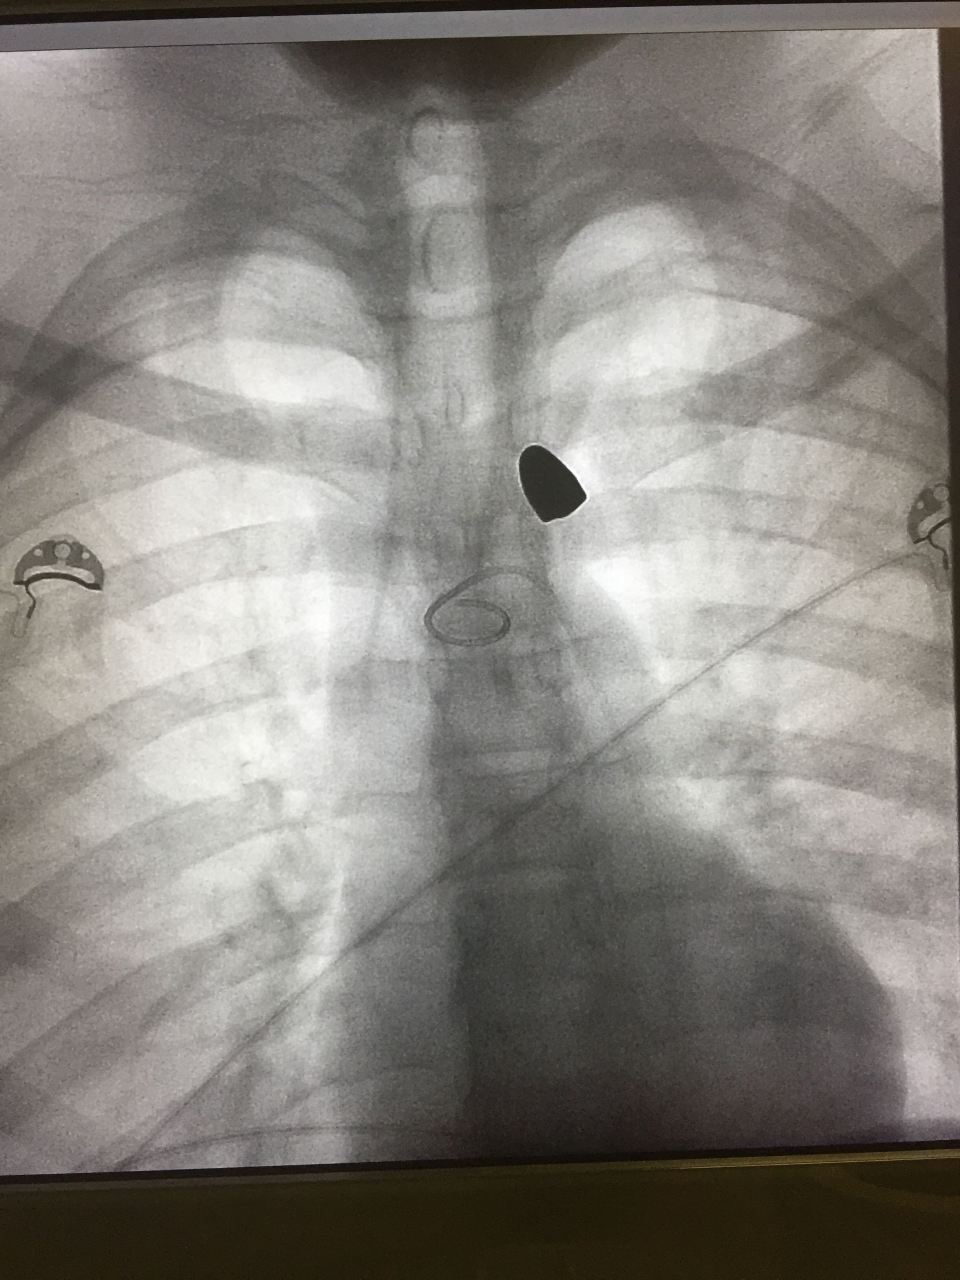

IMG_3920